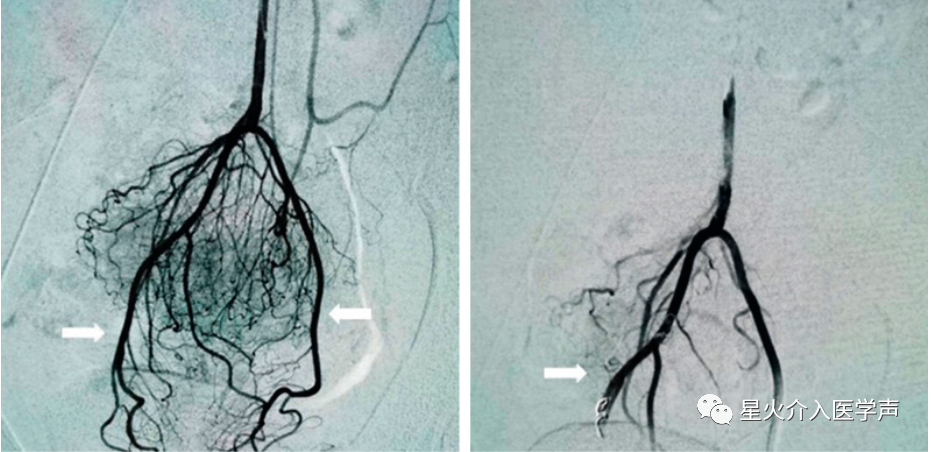

局麻后,采用改良Seldinger法穿刺右股动脉,然后插入4-Fr导管鞘。然后,使用4-Fr Simmons导管(Cordis,迈阿密湖,佛罗里达州)对肠系膜下动脉进行插管,使用2.7-Fr微导管(Terumo,Tokyo,Japan)对SRA及其分支进行超选择性血管造影(图1a,a,2a)。2a)。将适量明胶海绵颗粒(350–560 μm,艾丽康,杭州,中国)或微球(300–500 μm,恒瑞医疗,苏州,中国)注入靶动脉,然后,使用几个2-3 mm金属弹簧圈(美国印第安纳州布卢明顿市)。栓塞剂的总剂量和弹簧圈数由两名介入放射科医师达成共识确定。当痔丛动脉血管床消失后,栓塞术终止(图1b、b、22b)。

图 2内痔患者痔动脉血管造影特征。a减影动脉造影显示直肠血管强化(白色箭头);b最终动脉造影显示使用弹簧圈和微球栓塞两种SRA后,直肠下部血管减少(白色箭头)